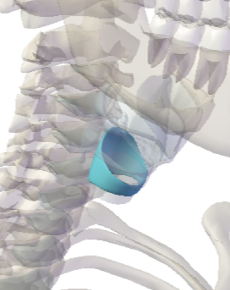

Thyroid cartilage

Cricoid Cartilage

Epiglottis